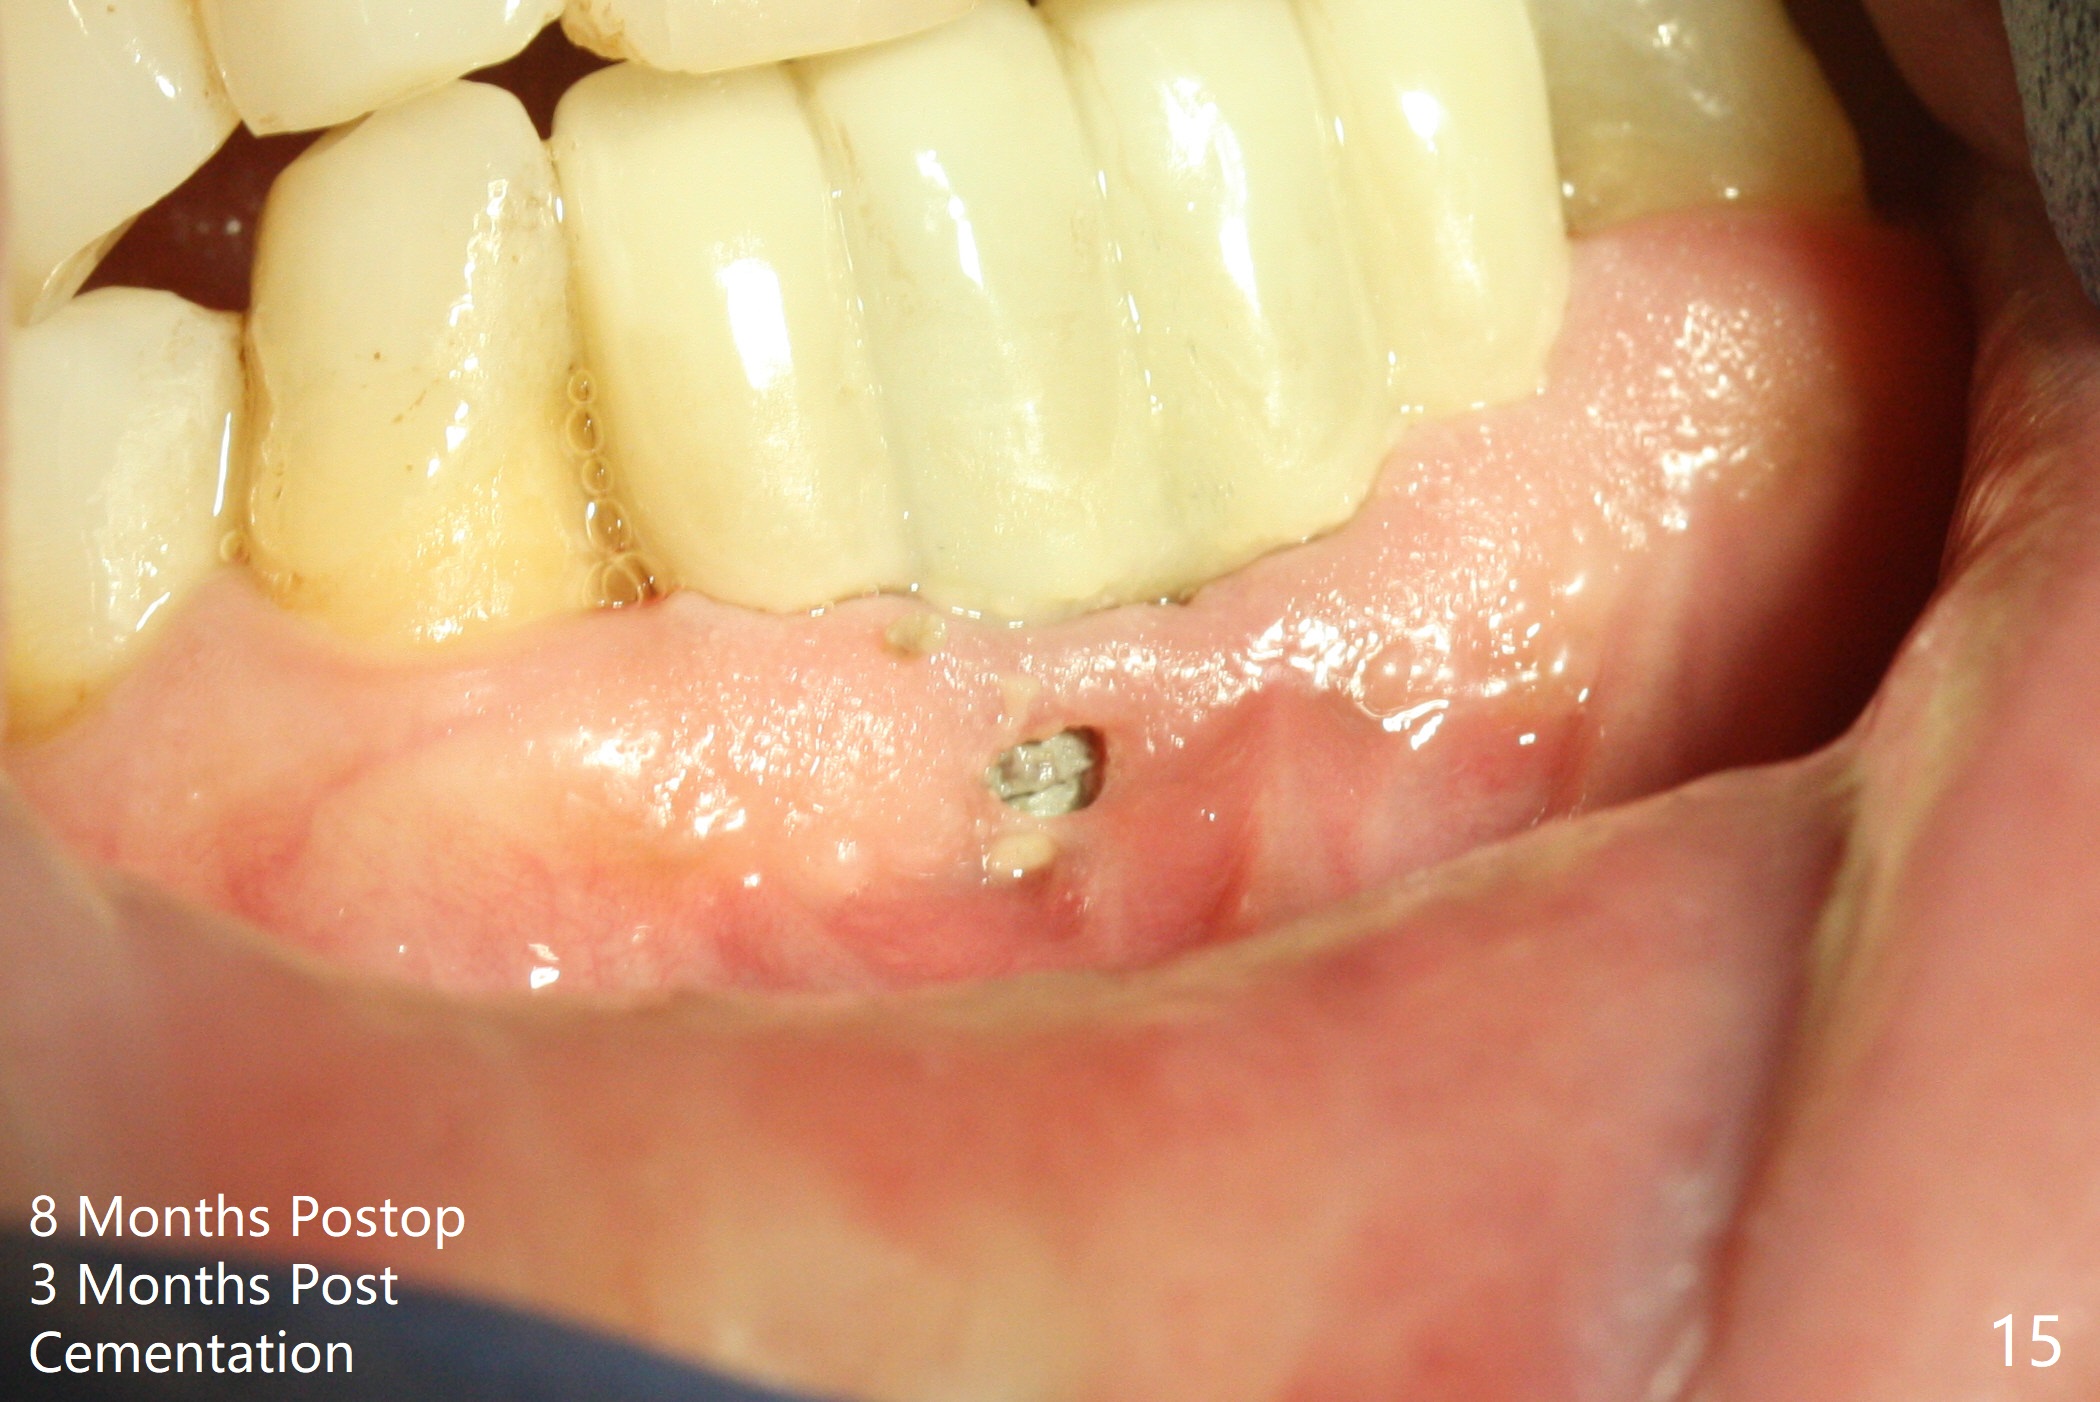

When the patient (smoker) returns for treatment, the apical abscess associated with #25 and 26 reduces with oral Amoxicillin. He agrees with 4 incisor extraction because of 2 apical fistulae (Fig.1 >). Osteotomy starts at the central incisor sockets due to mesial root exposure of the canines (Fig.2 arrowheads) and buccal alveolar bone fracture between #23 and 24 (Fig.7). Two of 3x14(4) mm 1-piece implants are placed with ~ 2 mm buccal gap (Fig.3). After Vanilla graft is placed in the bony defects (Fig.5 *) and Osteogen plug, sutures are placed (Fig.4). The implants are then placed deep to decrease thread exposure (Fig.6). Periodontal dressing is applied instead of provisional. Alveolar bone fracture between #23 and #24 accounts for why an implant is less suitably placed at #24 (Fig.7). Three months postop, composite is added to the pontic areas of the provisional (Fig.8 *). When the provisional is seated, the convex pontics press the used-to-be-flat gingiva (Fig.9 arrows). Thus the concave gingiva forms (Fig.10 *) with corresponding papillae (^). In fact the photos of Fig.8-10 is taken ~3 weeks later. Most of the grafted bone remains in place 3.5 months postop (Fig.11). A piece of floss with 2 knots in one end is placed between the middle units of the final bridge before cementation (Fig.12 (4 months 10 days postop)). In fact removal of residual cement is not so simple. It is tedious (Fig.13,14). An asymptomatic buccal fenetration with implant thread exposure is found 2 months post cementation and persists for another month in spite of advice to reduce smoking (1/2 ppd) and use of water pik (Fig.15). The area will be debrided, followed by bone graft and PRF in a month.